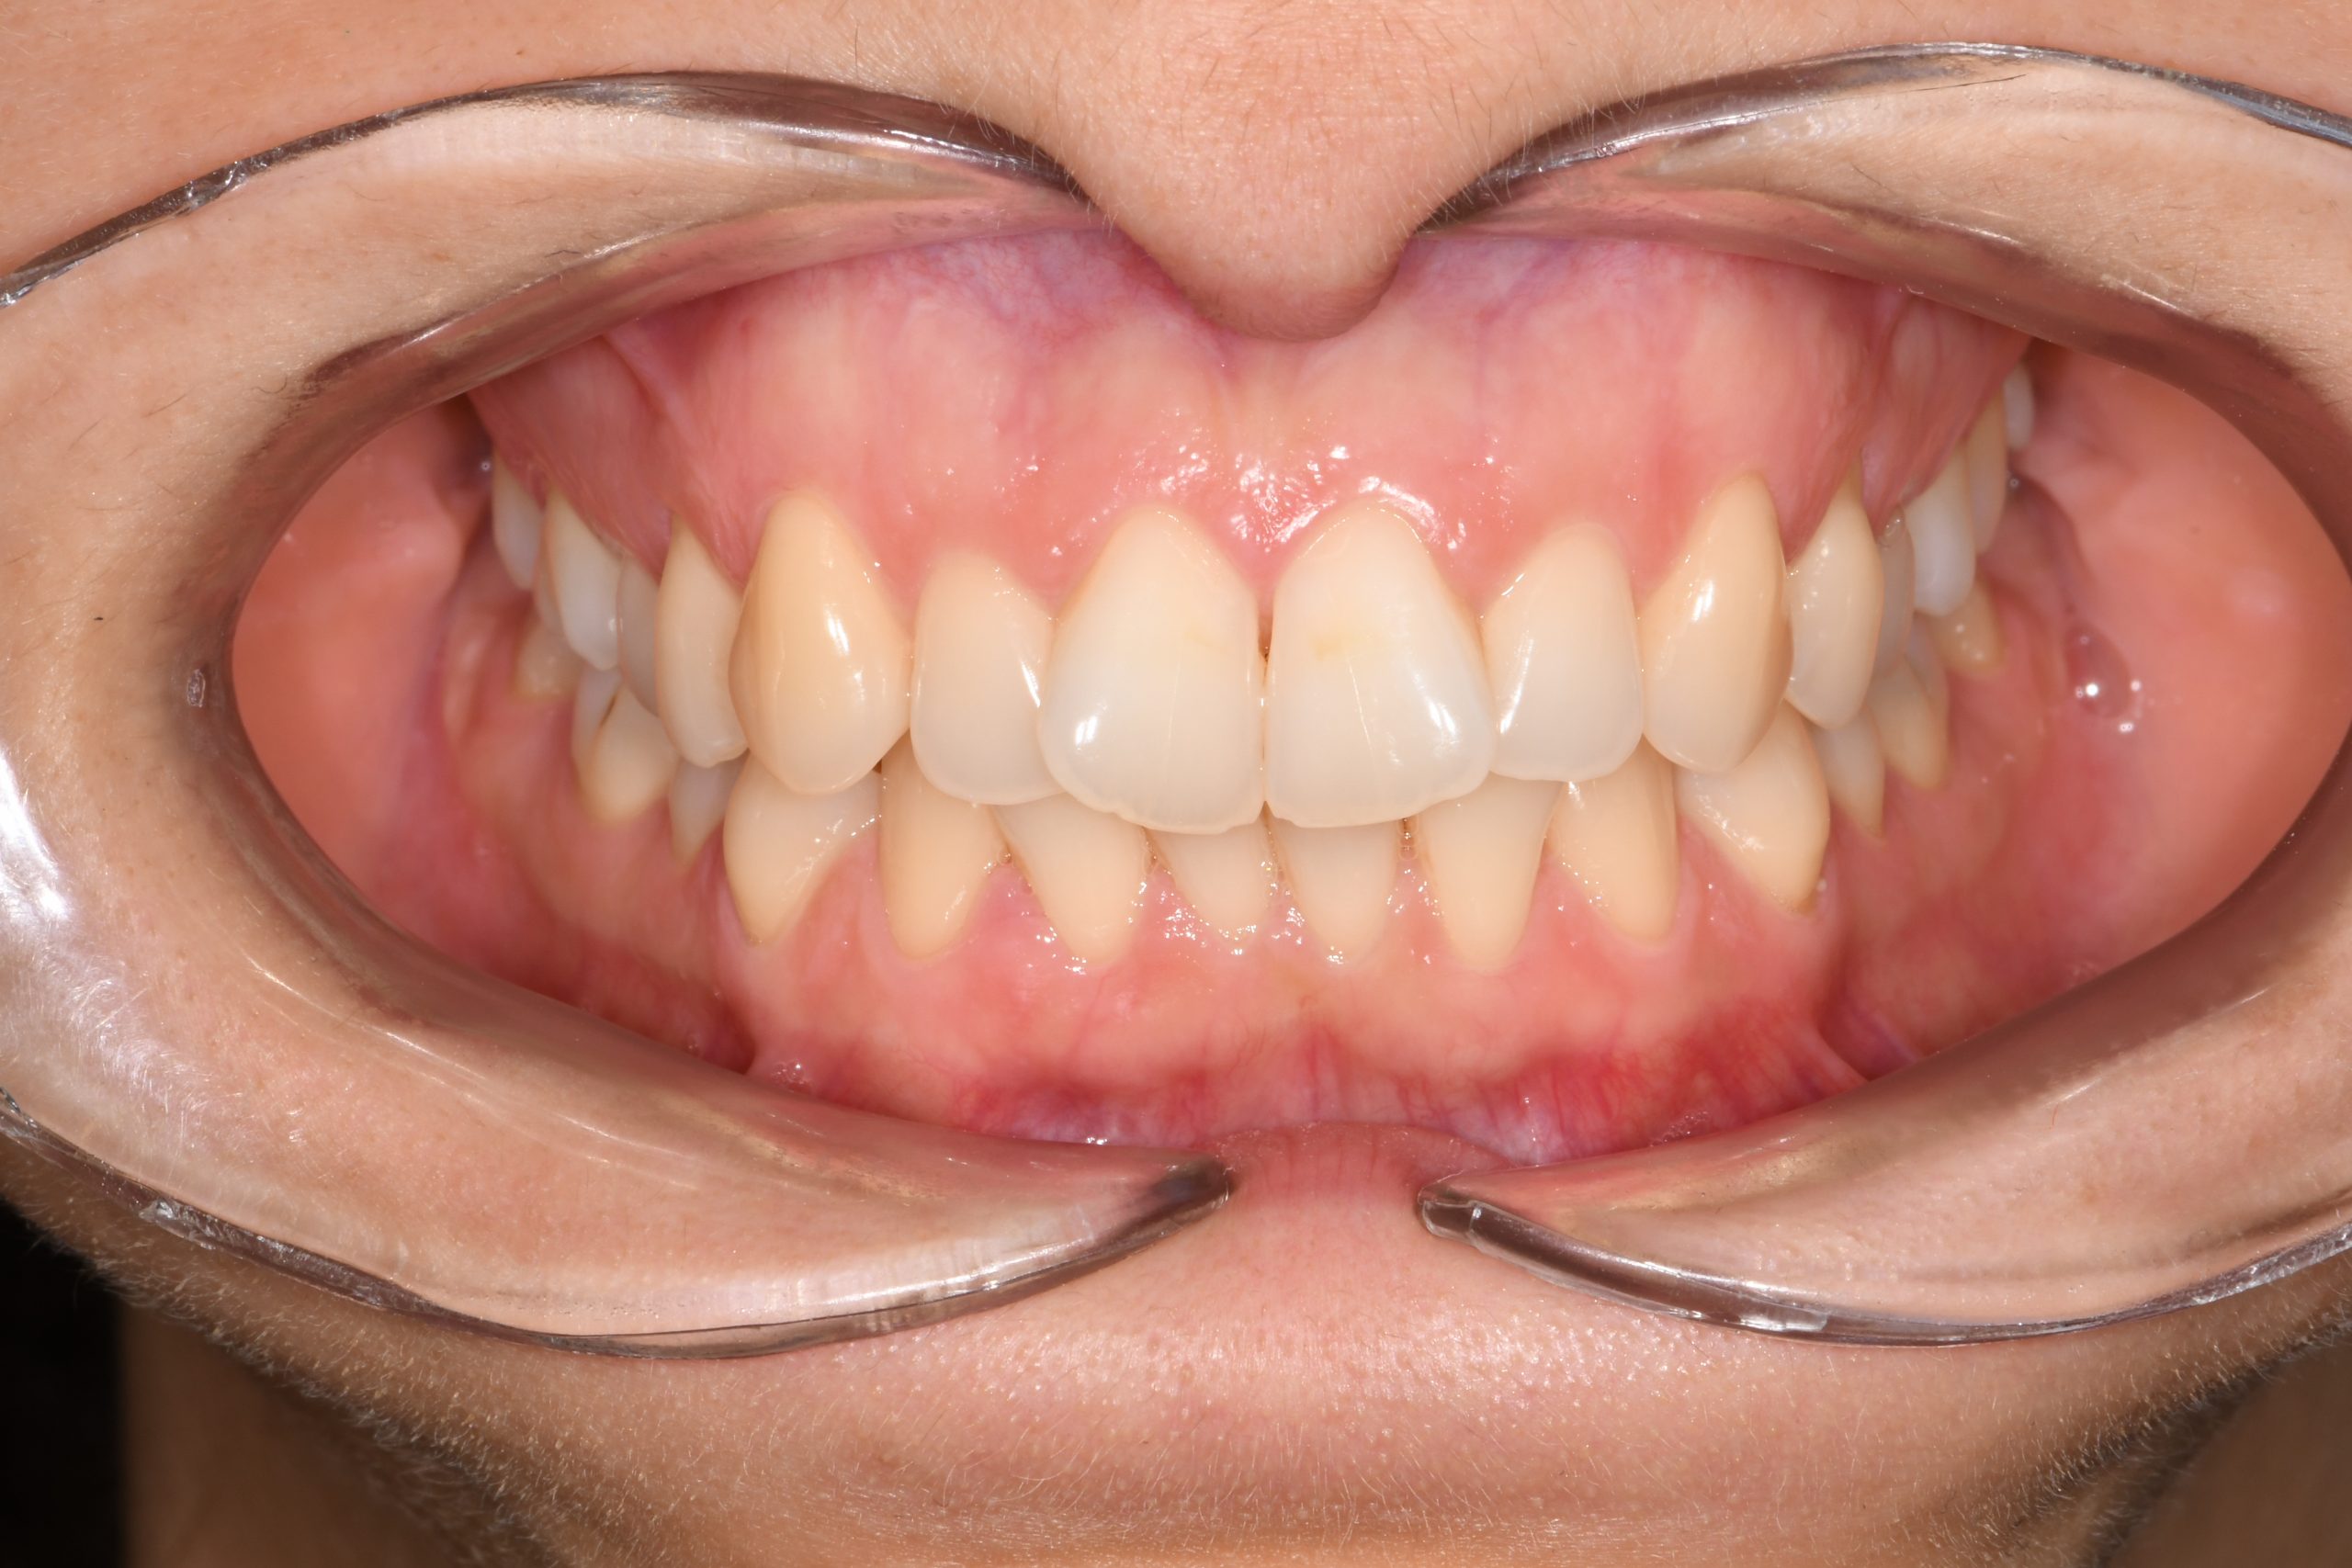

Az elmúlt évekből rengeteg szakmai referenciát tudnánk bemutatni, amelyek különböző fogszabályozási problémákat oldottak meg. Válogatva a több száz esetből, ezen az oldalon olyan képeket, információkat igyekeztünk bemutatni, amelyeknek a segítségével a jövőbeni pácienseinknek azt tudjuk üzenni: A Te fogsorod is lehet gyönyörű!

(Képeket a Pácienseink külön írásos beleegyezésével mutatjuk be!)